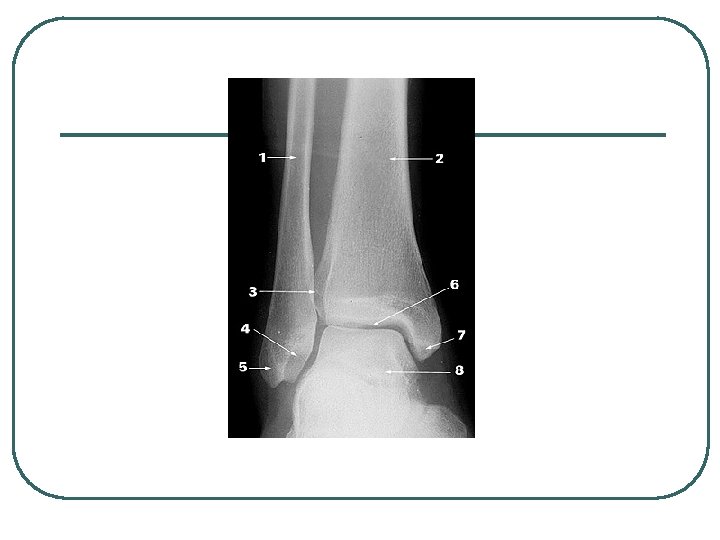

Stress Fractures l l l Bone remodeling Repetitive stress weakens the bone 10 -20% of injuries to athletes Most common locations: tibia, fibula and metatarsals. Tibial and fibular stress fractures can develop from “shin splints”

Diagnosis (FYI) l l l X-ray MRI CT scans

Ankle Sprains l l Most common athletic injury. 25% of all injuries. The risk of ankle sprains varies with the sport • 21 -53% basketball, 17 -29% soccer, 25% volleyball. Ankle sprains account for 10% to 15% of all lost playing time The medial malleolus is shorter than the lateral mallelous so there is naturally more inversion than eversion.